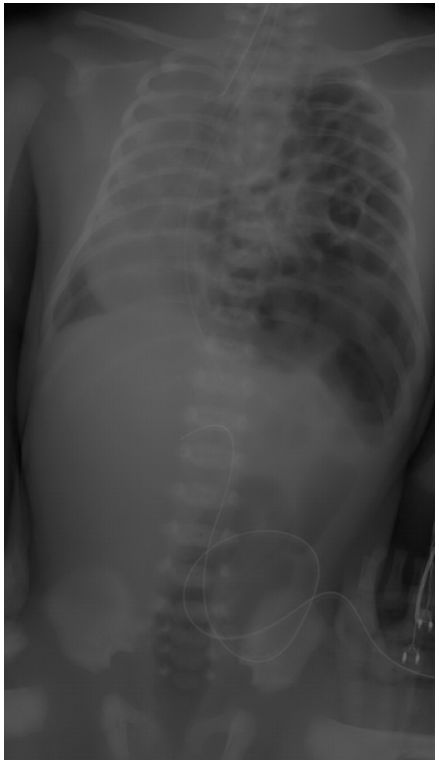

74.足月產新生兒因呼吸急促住進新生兒加護病房,胸腹部X光如附圖,則最可能的診斷為下列何者?(A)橫膈疝脫(diaphragmatic hernia) (B)左側氣胸 (C)胎便吸入(meconium aspiration) (D)右肋膜積液(E)一律給分